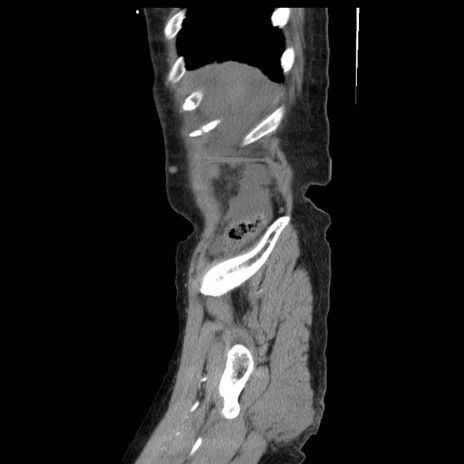

症例1(矢状断像)

【症例】80歳代女性

【主訴】腹痛

【現病歴】8時間前から腹痛あり来院。

【既往歴】糖尿病、脂質異常症、子宮体癌にて子宮全摘術

【身体所見】意識清明・会話良好だが腹痛で苦悶様、全腹部にわたって反跳痛と圧痛あり

【データ】WBC 13600、CRP 0.14、LDH 224、CK 90